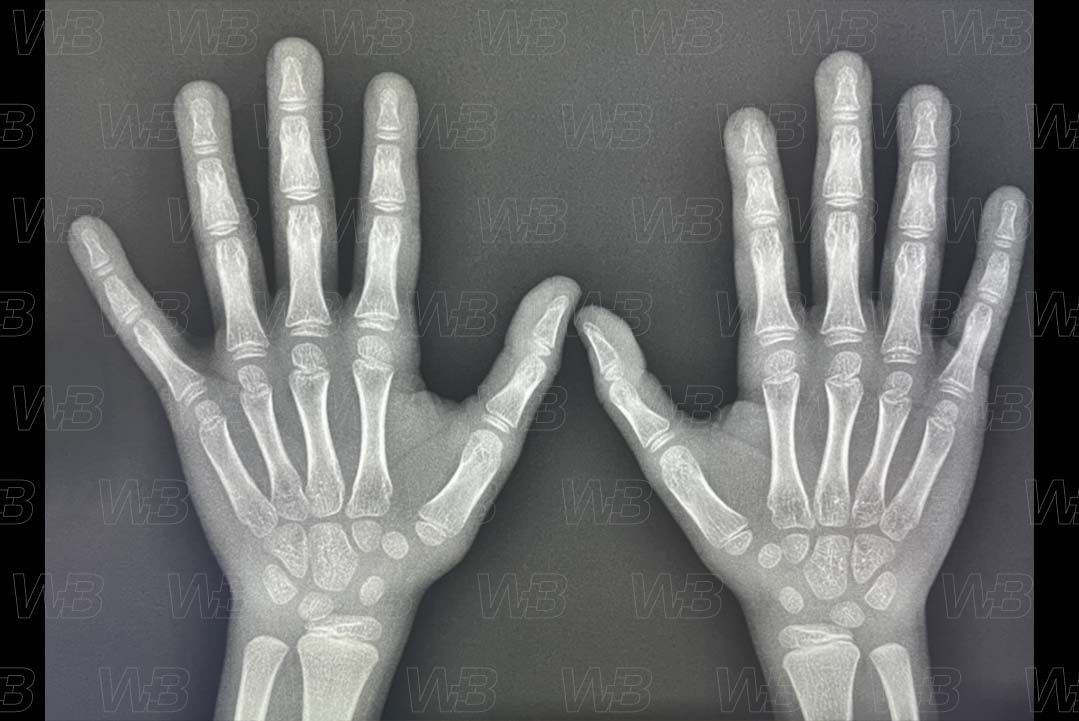

RADIOGRAFIA MÃOS E PUNHOS (IDADE ÓSSEA)

Feminino

5 anos e 9 meses:

• Sobreposição de hamato e capitato;

• É maior a metade lateral da epífise do rádio.